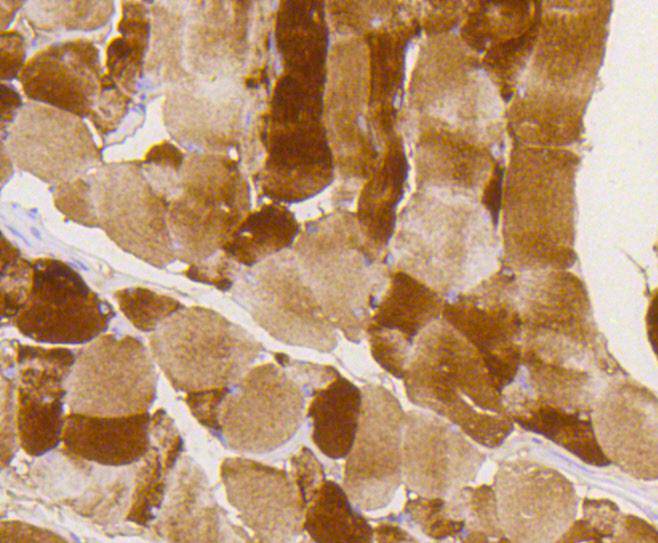

Immunohistochemical analysis of paraffin-embedded mouse smooth muscle tissue using anti-Phospho-Glycogen synthase 1(S641) antibody. Counter stained with hematoxylin.